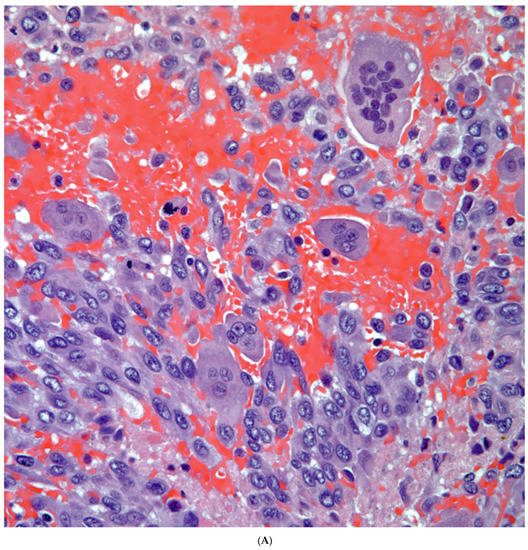

Giant Cell Carcinomas: These tumors may show predominantly a neoplastic cellular proliferation composed exclusively of multinucleated giant cells or a predominantly giant cell carcinoma (Figure 5A,B) or associated with a conventional non-small cell carcinoma like adenocarcinoma or squamous cell carcinoma. The giant cell carcinoma may show giant cells of the syncytiotrophoblastic, osteoclastic, or null cell type. The giant cell carcinomas of the null cell type characteristically show a prominent inflammatory background and giant cells engulfing inflammatory cells (emperipolesis) (Figure 6A,B). The tumors composed of osteoclast-like giant cells show giant cells like those described in bone tumors (Figure 7A,B).

Figure 5.

(A) Predominantly giant cell carcinoma; (B) Marked atypia and numerous multinucleated malignant giant cells.